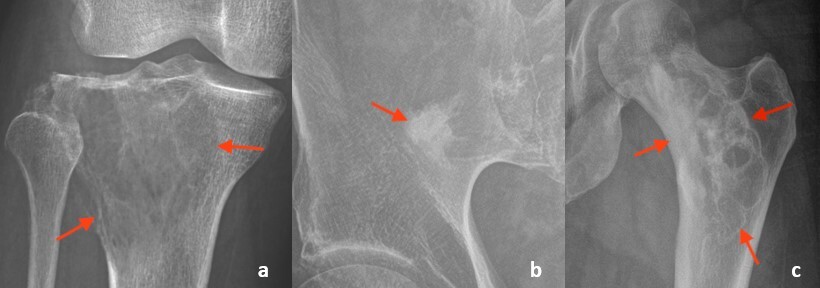

6. The presence and type of periosteal reaction can also help identify aggressive pathology.

Periosteal reaction is a response of the periosteum to an insult to the underlying bone (Figure 3).6 Solid periosteal reaction is seen in the setting of a slow-moving, indolent process, where the periosteum has time to develop smooth, organized bone. In contrast, a fast-moving, aggressive process does not allow for well-organized periosteal bone formation. This can result in periosteal reaction that appears lamellated (onion skin), perpendicular spiculated (hair-on-end), or divergent spiculated (sunburst), sometimes with a Codman’s triangle, all of which can be seen with aggressive processes like malignancy and infection.